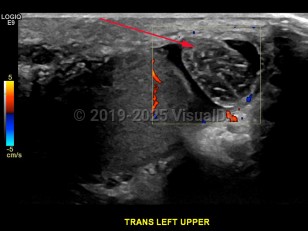

Imaging Studies image of Testicular torsion - imageId=6840062. Click to open in gallery.  caption: '<span>Transverse color Doppler image of superior aspect of left testicle, demonstrating torsion of epididymal appendage</span>.'

Transverse color Doppler image of superior aspect of left testicle, demonstrating torsion of epididymal appendage.